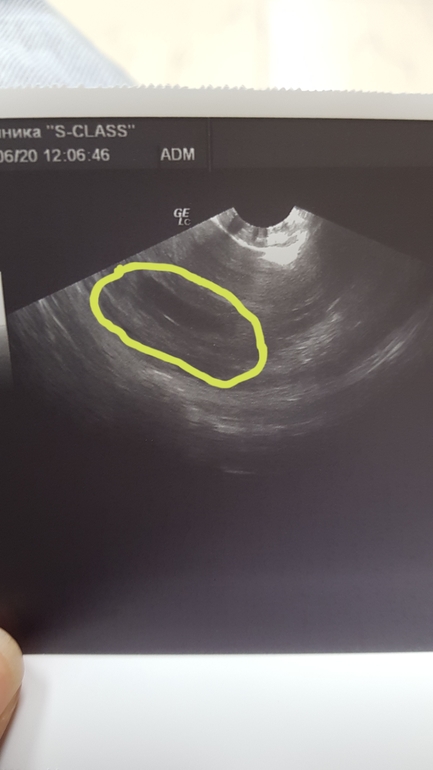

Первый снимок пузожителя

Вчера была на УЗИ.очень переживала из-за мазни вот и побежала в платную клинику на УЗИ.Срок маленький 6 недель.сказали что эмбриона еще пока нет.но через пару дней уже должен появиться.И предложили снимок пузожителя сделать для папы.Естественно согласилась.пришла домой показала мужу снимок.Долго смотрел на снимок потом задал вопрос :а где наш пузожитель? Конечно было смешно от такой реакции.